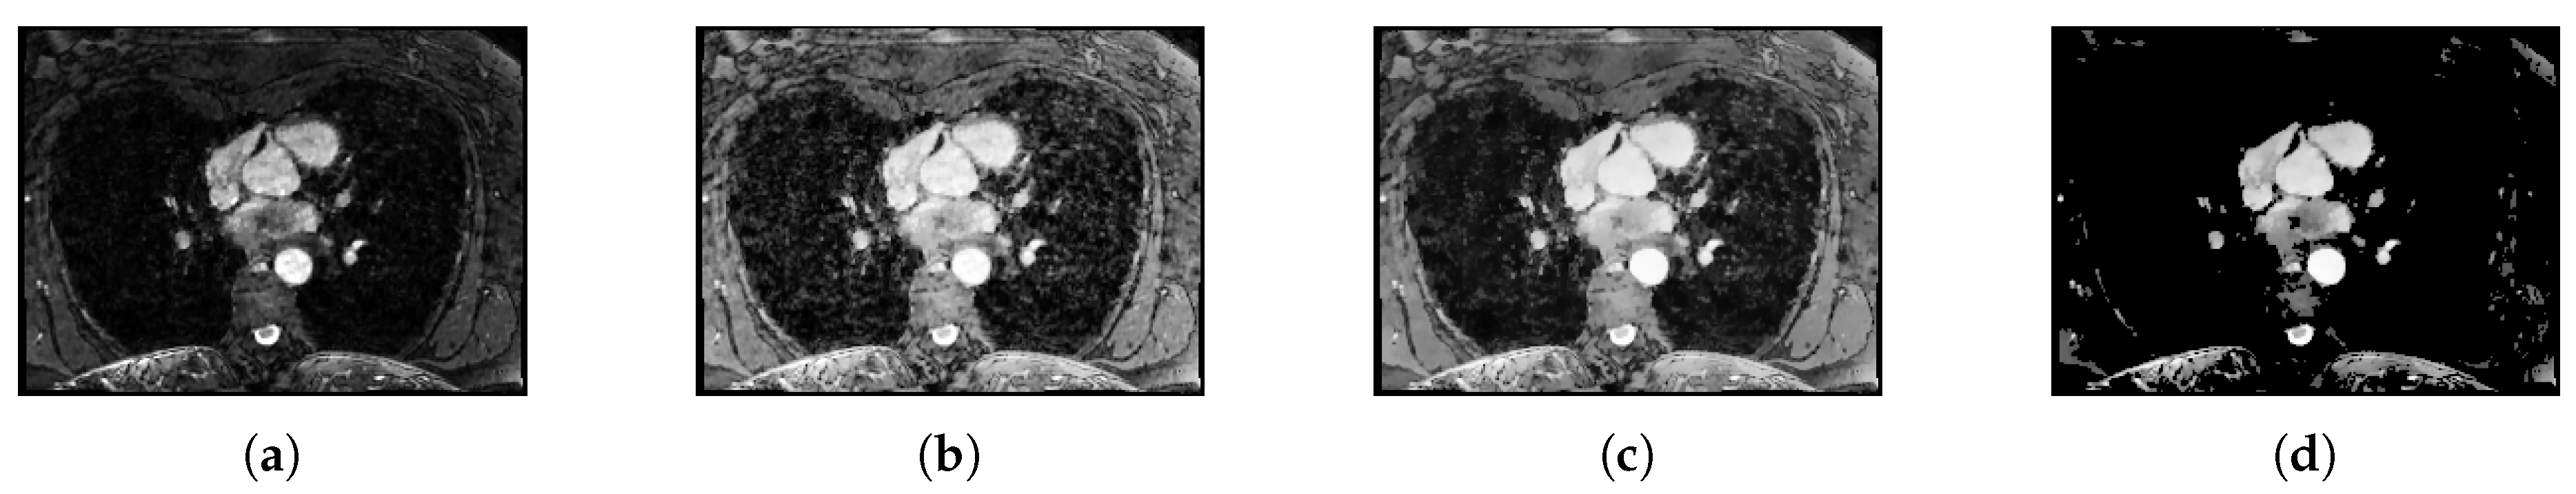

3.2. Preprocessing

3.3. Aorta Segmentation

3.4. Vessel Enhancing Filtering

3.4.1. Entropy-Supported Medialness Measure

3.4.2. Tubeness Measure

3.5. Ostia Detection